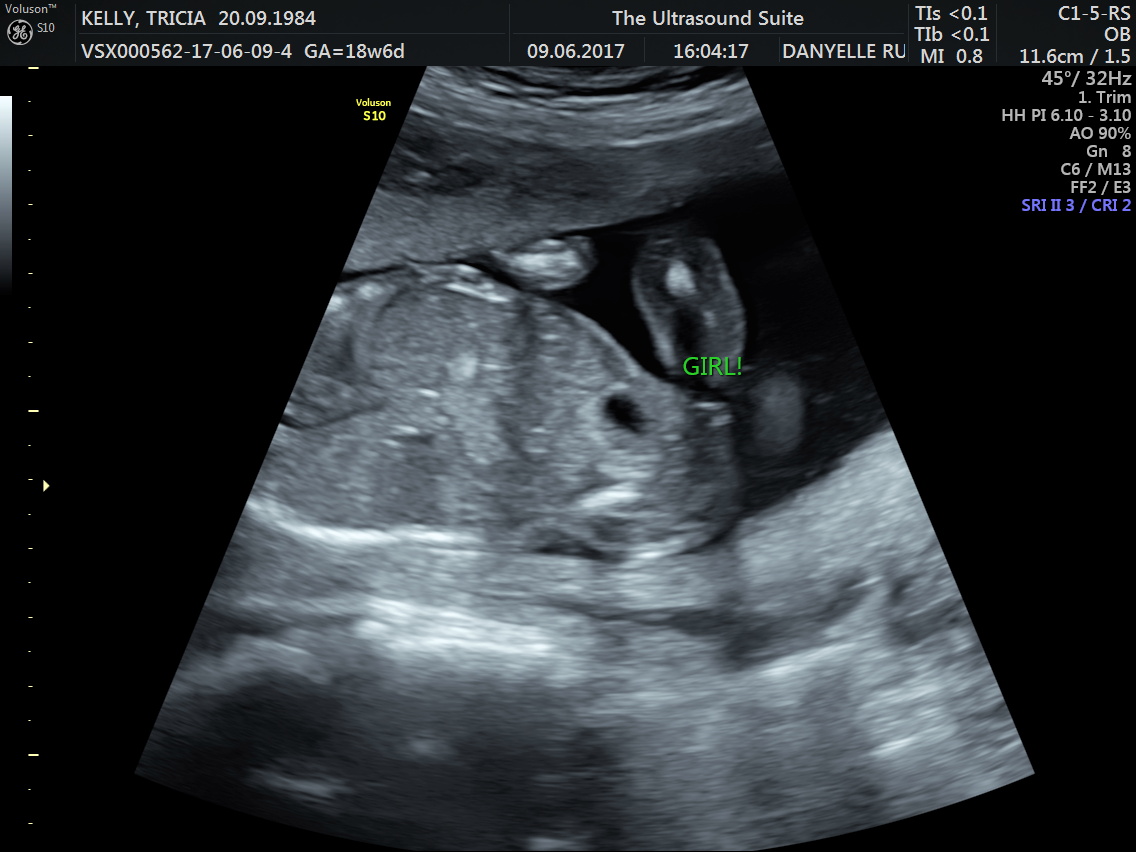

Despite the fact that sonographers are experts in their field, estimated due dates (EDD) calculated from pregnancy scans can be incorrect, as Ollysmum76 discovered . "My due date got put back by 2 weeks at the 12 week scan . Original date given was 18 December but at the scan it was moved to 31 Dec .

My dating scan puts me at 19 weeks 6 days which according to my 20 week scan yesterday is exactly what baby is measuring at . I had a period on the 13th if august but according to my dating scan I conceived on the 4th of August so everyones been telling me it was an implantation bleed which might be what you had .

The dating scan is usually done at some point between 8 weeks and 14 weeks pregnant .NICE recommends it's done between 10 weeks and 13 weeks . You will have had earlier appointments and may have had an early scan if you've had any concerns such as bleeding, but otherwise this is the first time you'll get to see your baby, so it's a real milestone in your pregnancy .

This is called the dating scan . It's used to see how far along in your pregnancy you are and check your baby's development . The scan may also be part of a screening test for Down's syndrome . Your midwife or doctor will book you a dating scan appointment . It will usually take place at your local hospital ultrasound department . Most scans are carried out by sonographers . You may need to have a full bladder for this scan , as this makes the ultrasound image clearer .